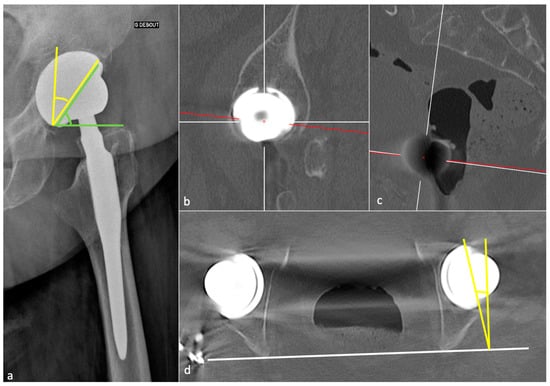

3.3.1. Acetabular Side

| Measurement | Normal Value | Consequences of Mispositioning |

|---|---|---|

| Frontal acetabular inclination | 40 ± 15° | - Decreased: hip abduction limitation |

| - Increased: dislocation risk | ||

| Sagittal acetabular inclination | 35–40 ± 10° in standing position | - Increased: posterior impingement, anterior dislocation |

| 52 ± 11° in sitting position | - Decreased: anterior impingement between the cup and the neck, posterior dislocation | |

| Acetabular anteversion | 5–25° | - Lack of anteversion or retroversion: posterior dislocation, iliopsoas impingement |

| - Excessive anteversion: anterior dislocation | ||

| Acetabular center of rotation position | Similar to the contralateral hip | Lateralized: dislocation risk |